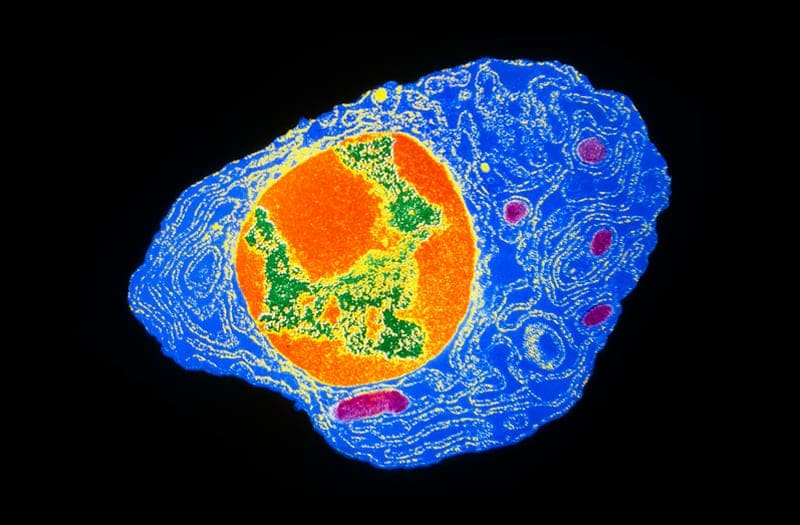

Por Primera Vez, Los Científicos Han Secuenciado Por Completo Un Cromosoma Humano

Imagine tener que reconstruir un rompecabezas. Si está trabajando con piezas más pequeñas, cada una contiene menos contexto para averiguar de dónde vino, especialmente en partes del rompecabezas sin pistas únicas, como un cielo azul. Lo mismo es cierto para la secuenciación del genoma humano. Hasta ahora, las piezas eran demasiado pequeñas y no había forma de unir las partes más difíciles del rompecabezas del genoma.